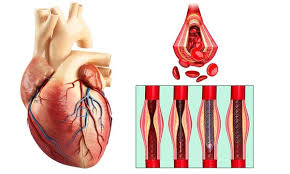

Value added benefits of the Coronary Angioplasty:

Ø Doctor consultation charges

Ø Lab tests and diagnostic charges

Ø Room charges inside hospital during the procedure

Ø Surgeon Fee

Ø Nursing charges

Ø Hospital surgery suite charges

Ø Anesthesia charges

Ø Routine medicines and routine consumables (bandages, dressings etc.)

Ø Food and Beverages inside hospital stay for patient and one attendant.

Extra benefits:

ü Interpreter

ü Visa assistance

Ø Site tourism of the city

Ø Follow up with the doctor

Ø Airport pick up and drop

Ø Free online consultation with the doctor

Ø Priority appointments with the doctor

Ø Room upgrade from sharing to private